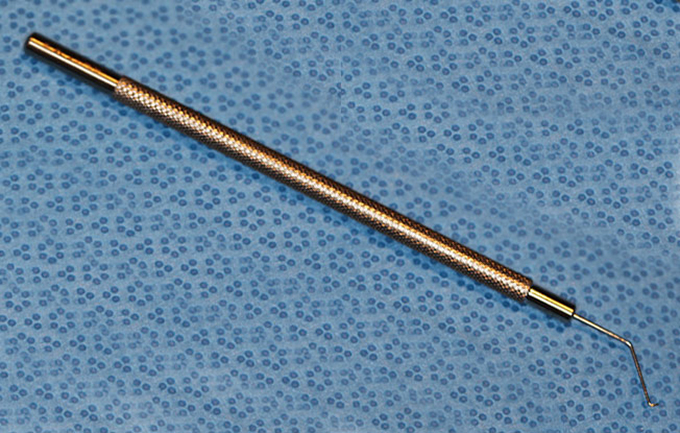

Kuglen Hook, straight, round handle

Kuglen

Catalog: Katena K3-5522

Typical Use(s): Position IOL and haptics; Fix eye with paracentesis; Retrieve suture from AC